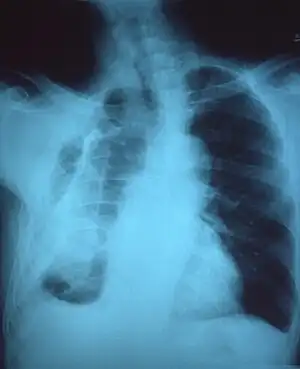

If a fibrothorax is severe, the thickening may restrict the lung on the affected side causing a loss of lung volume.[7] Additionally, the mediastinum may be physically shifted toward the affected side.[3] A reduction in the size of one side of the chest (hemithorax) on an X-ray or CT scan of the chest suggests chronic scarring.[6] Signs of the underlying disease causing the fibrothorax are also occasionally seen on the X-ray.[6] A CT scan may show features similar to those seen on a plain X-ray.[7] Lung function testing typically demonstrates findings consistent with restrictive lung disease.[6]

Extensive left-sided fibrothorax

Chest radiograph displaying inhomogeneous opacification of the left half of the chest that is fibrothorax